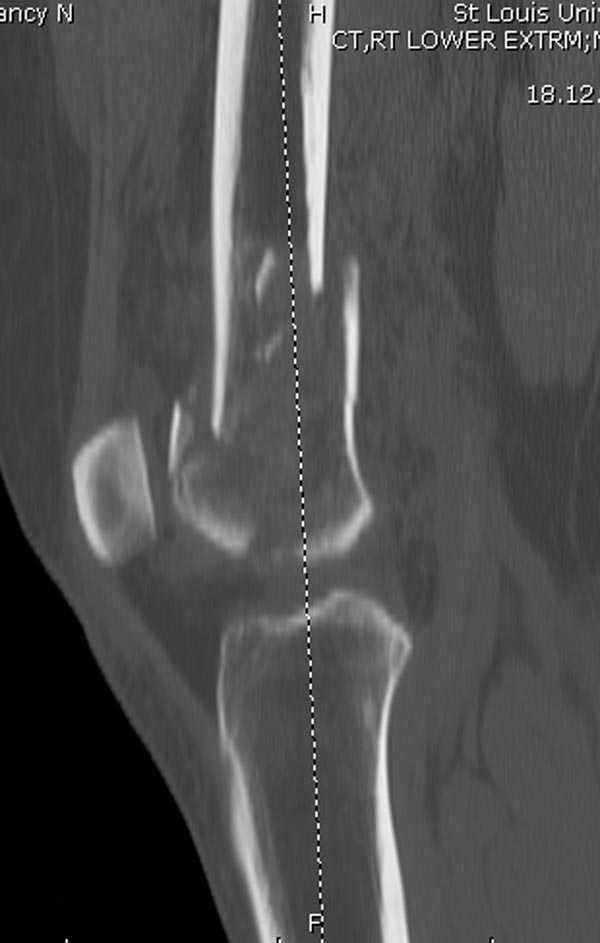

[Ortho] Дистальный перелом бедра

Бесспорно, предлагаемый ретроградный метод имеет свои преимущества, но имеется опасность при манипуляции интрамедуллярным гвоздем расколоть мыщелки.

Раскол можно предупредить шурупами, но короткий дистальный фрагмент навряд ли позволит добиться адекватной стабильности конструкции. Стандартные гвозди не рассчитаны для таких переломов, и если все таки желаете провести фиксацию гвоздем, тогда надо заказывать специальный custom made nail т.е. с расширенной возможностью дистальной блокировки.

Поэтому такие меж и над- мыщелковые переломы более предпочтительным считается фиксировать мыщелковыми пластинами